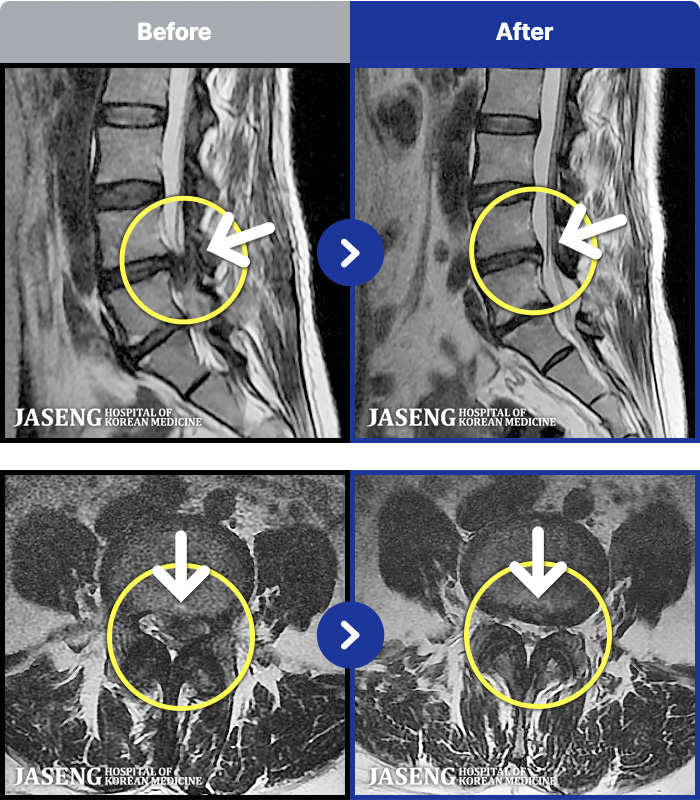

- MRI ġ

MRI ġ

1,240 MRI ũ ʸ Ȯϼ.